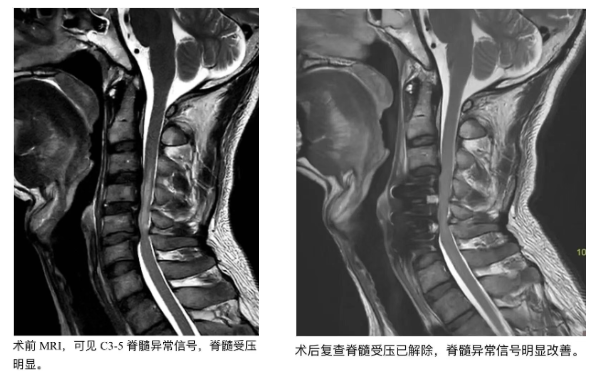

2025年8月9日傍晚,赖先生下班回家由于不慎踩空摔倒,致颈部脊髓严重损伤。尽管当地医院紧急实施手术稳住了脊柱,但术后的他却陷入更大困境—— 四肢毫无力气,别说站立行走,就连坐起身都无法独立完成,大小便也需他人辅助,生活完全失去自理能力。

针对赖先生的病情,省二医云浮医院中医康复科团队首先进行了全面评估,并定制了一套个体化康复方案—— 不仅包含肢体被动活动、主动肌力训练、平衡与步态矫正等现代康复手段,还创新融入针灸、推拿、理疗等中医特色技术,形成“中西医结合”的康复体系。